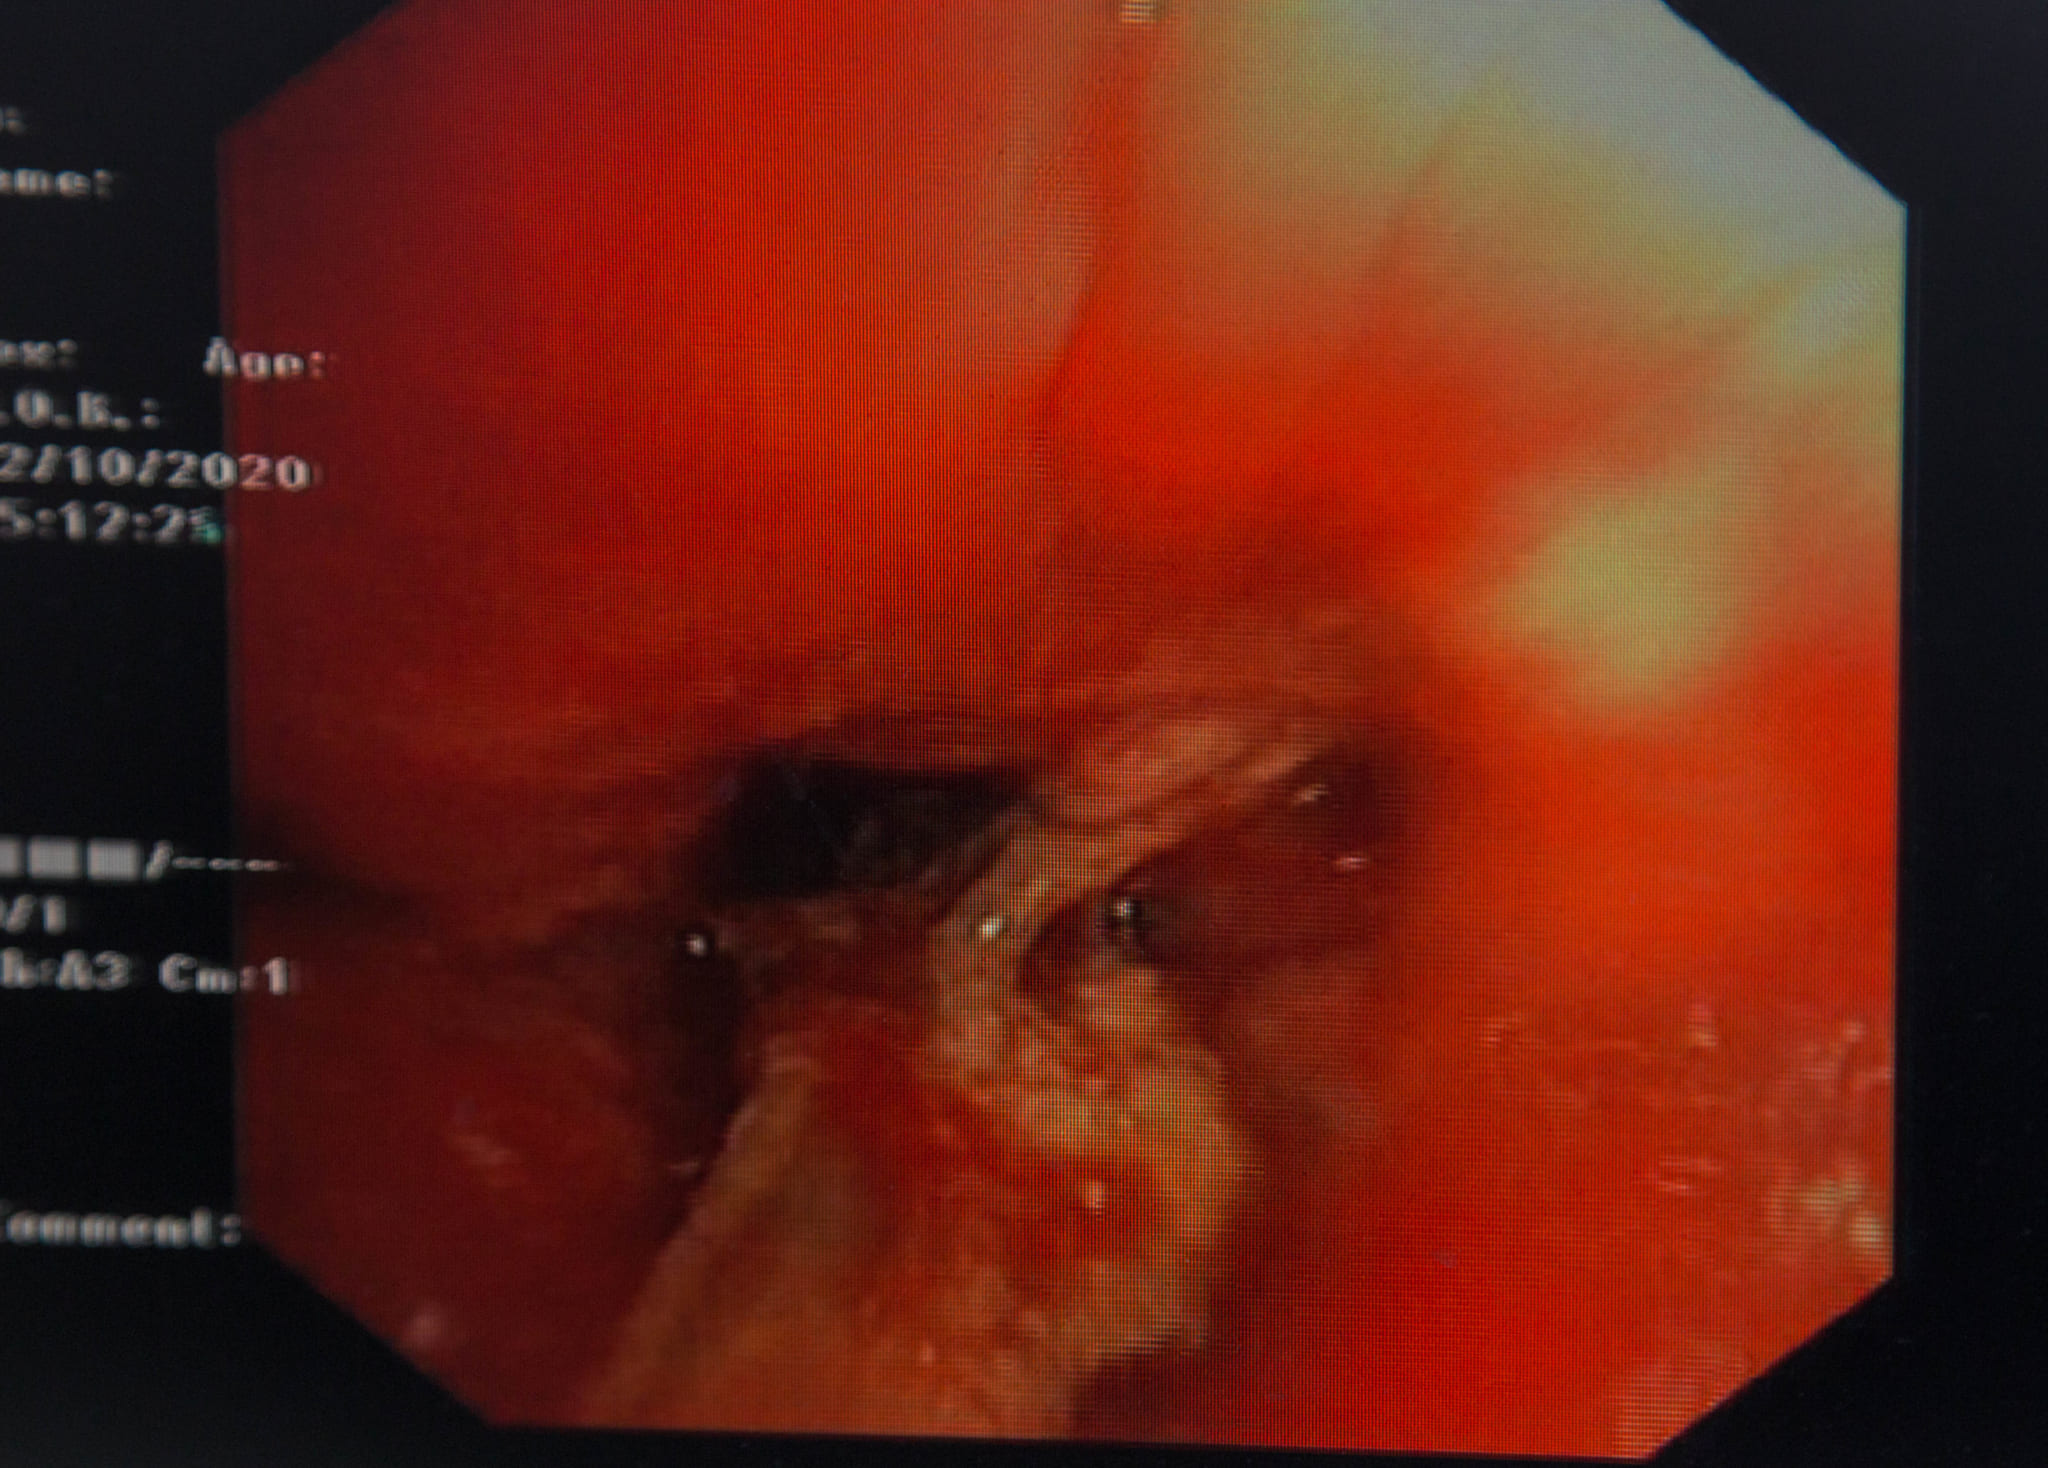

Bệnh nhân được BSCKII Lê Thị Trâm, Trưởng Đơn nguyên Chăm sóc toàn diện thăm khám và qua nghe phổi, bác sĩ đã nghe thấy tiếng rít phế quản ở phổi phải người bệnh. Bệnh nhân đã được chỉ định chụp CT, phát hiện nghi tổ chức cản quang nằm trong lòng phế quản thùy dưới phổi phải. Tiến hành nội soi phế quản, phát hiện thấy phế quản trung gian nhiều tổ chức sùi, chảy máu trong lòng phế quản, nhìn thấy dị vật là mảnh xương nằm vắt ngang phế quản thùy dưới phổi và một phần áp sát phế quản trung gian. Có nhiều mủ chảy ra ở phế quản thùy dưới.

Bệnh nhân đã được BSCKII Lê Thị Trâm, Trưởng Đơn nguyên Chăm sóc toàn diện cùng kíp thực hiện tiến hành nội soi phế quản gắp dị vật, cầm máu. Chỉ sau 30 phút, bác sĩ đã gắp thành công dị vật là mảnh mang xương cá, kích thước 2cm ra khỏi phế quản phải cho bệnh nhân. Ngay sau thủ thuật, tình trạng sức khỏe người bệnh ổn định, đỡ ho, không tức ngực và hết khó thở.